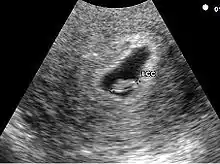

- La visualisation de la vésicule vitelline qui affirme définitivement le caractère ovulaire de l'image échographique.

- La visualisation de la vésicule vitelline est un élément essentiel pour affirmer le caractère ovulaire de l'image et l'évolutivité de la grossesse. Embryologiquement, la vésicule vitelline visualisée correspond à la seconde vésicule vitelline. La vésicule vitelline est toujours visible à 5 semaines et 5 jours par voie endovaginale. Le sac ovulaire mesure en moyenne 8 mm. Par voie abdominale, elle est toujours visible à 7 semaines (le sac ovulaire mesure en moyenne 20 mm). Le diamètre de la vésicule vitelline augmente de 5 à 10 semaines pour atteindre 5 à 6 mm.

Embryon à 5 semaines

L'embryon est visible dès 5 semaines en cas d'utilisation de sonde endovaginale de haute fréquence. Il se présente comme une zone hyperéchogène coincée entre la vésicule vitelline et la paroi du sac ovulaire. Une activité cardiaque peut être visualisée. Il est déconseillé, à ce stade, d'utiliser le doppler pour entendre l'activité cardiaque embryonnaire en raison d'effet délétère possible sur la formation du cœur. En raison de la sensibilité humaine au mouvement, il est parfois possible de visualiser une activité cardiaque avant la visualisation de l'embryon. En pratique, l'activité cardiaque doit être systématiquement vue dès que l'embryon mesure 5 mm.